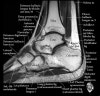

발목 관절의 MRI 단면 영상

- Sagittal section

Bones and marrow

Joint fluid

Talar dome

Subtalar joints

Achille's tendon

Sinus tarsi

Plantar fascia